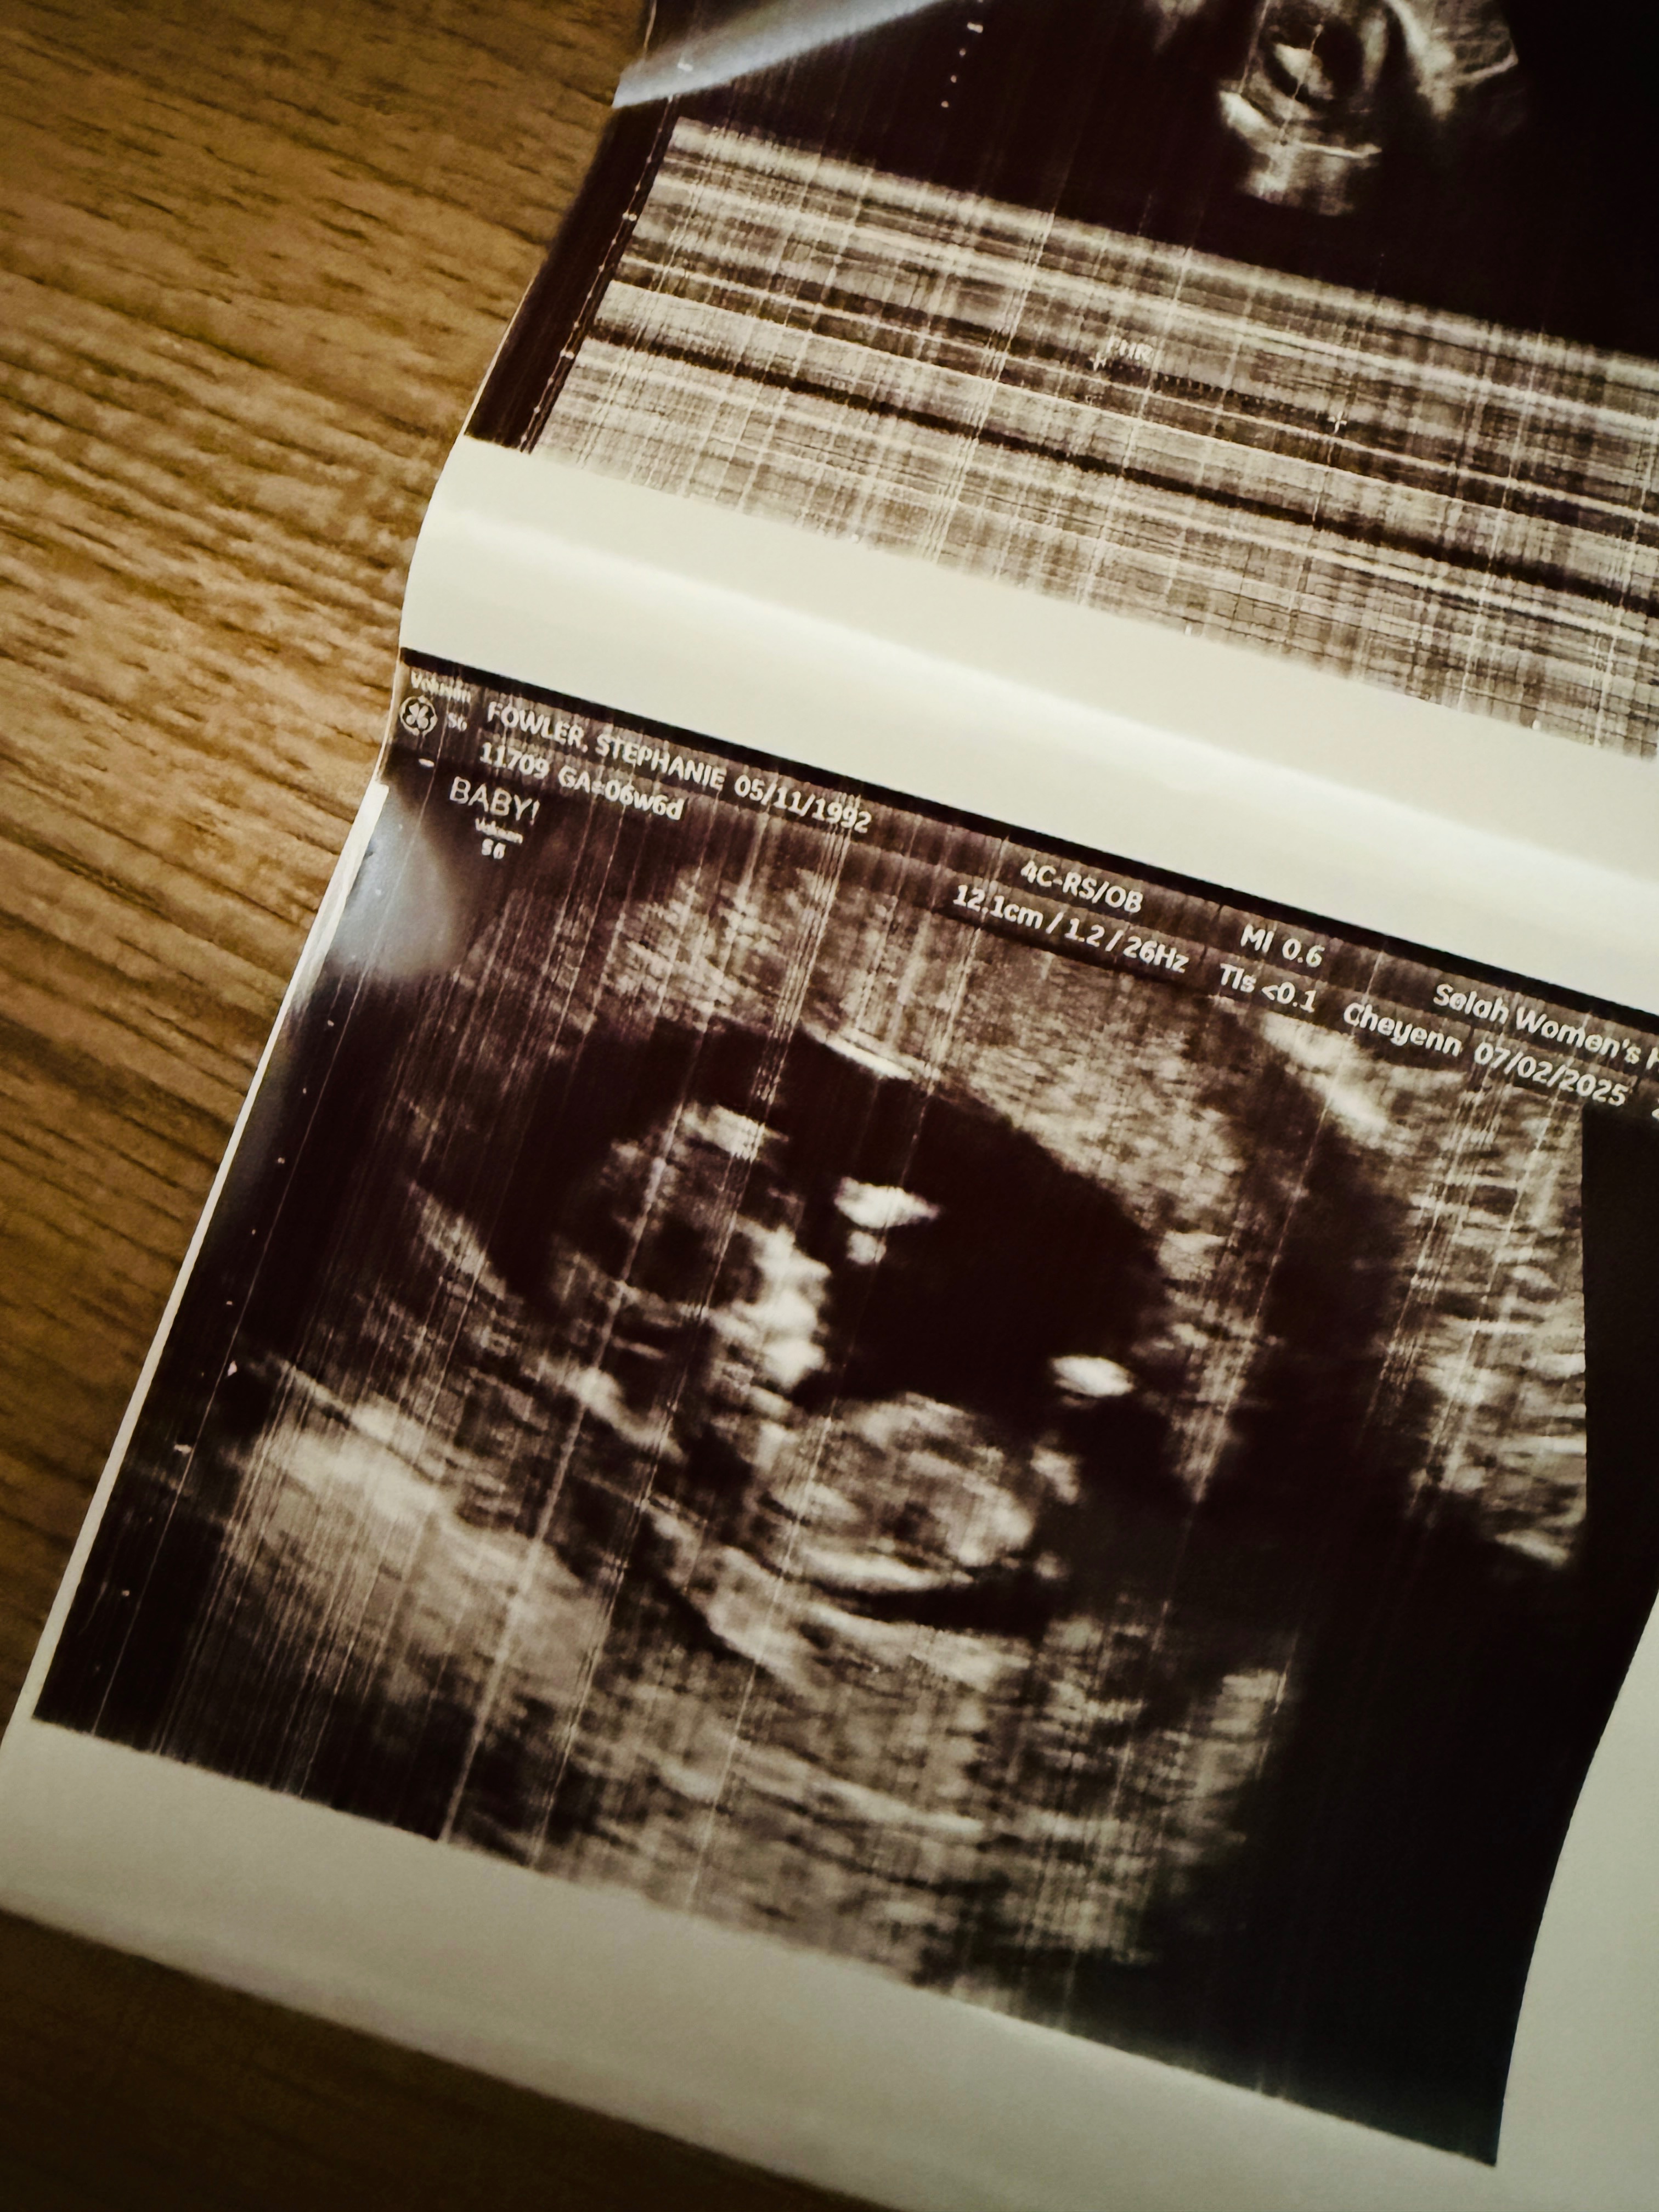

Stephanie and Victor had dreamed of becoming parents long before they said “I do.” When they learned this summer that they were expecting their first child, they were overjoyed. Soon after, however, test results devastatingly suggested they were likely miscarrying. In the face of that painful news, Stephanie and Victor fought to trust God with the outcome. Then at their first ultrasound, against all odds, their baby boy was alive and thriving—a moment that forever changed their story. From that point they have been grateful beyond words to continue enjoying a healthy pregnancy.